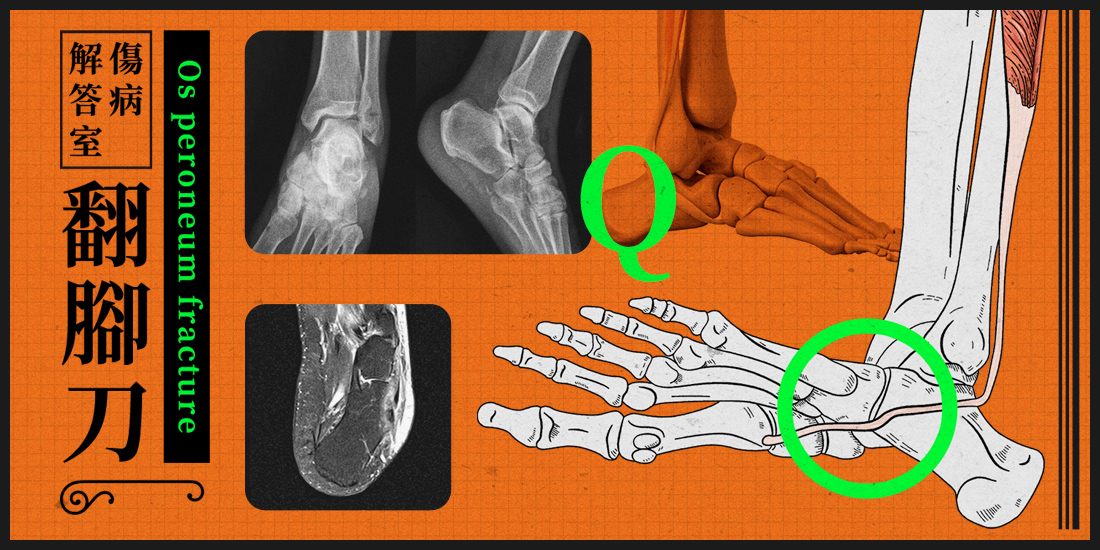

結果MRI答案出來是: Os peroneum fracture 腓骨肌附生骨撕裂傷合併肌腱斷裂。

附生骨顧名思義就是多出的一塊骨頭,功能就像髕骨一樣可以增加力矩讓肌肉發力更有效率。而Os peroneum 這個卵圓狀的小骨頭就剛好被包覆在腓骨長肌裡面,在骰骨上轉折並跟骰骨的關節面滑動。腓骨長肌一路從外踝後方、腳掌外側鑽入腳掌內,然後附著在第一趾骨基底。

Os peroneum或者附近的腓骨長肌,因外力(例如扭傷)而有可能有斷裂風險。也有些人的os peroneum在生長時沒有融合再一起,X光上看起來就像是兩顆種子骨(Bi-partie type)。這種情況會弱化os peroneum的結構,增加受傷的風險。雖然這個案例是急性受傷斷裂,但大部分反而是肌腱病變(tendinopathy)造成的問題,這種情況常見於過度使用、反覆受傷的人身上。也就是可能病人有好一陣子的外側腳掌疼痛的問題。或是足背屈合併足跟內翻時會有疼痛問題。